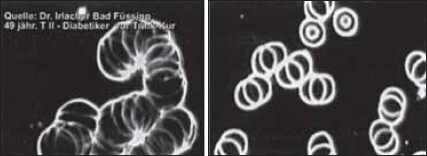

Настоящую сенсацию произвели в Германии недавние исследования доктора Ирлахера, посвященные влиянию живой воды на свойства крови и лечению живой водой состояний, обусловленных или отягощенных окислением. Для экспериментов использовалась техника «черного поля», или фазово-контрастной микроскопии. Об эффективности применения живой воды вы можете судить по приведенным ниже фотографиям (рис. 17–19).

Живая и мертвая вода – новейшее лекарство современности - i_022.jpg

Рис. 18. На левой фотографии видны патологические изменения эритроцитов у 49-летнего больного диабетом 2-го типа (монетное склеивание), на правой фотографии – кровь того же больного через 14 минут после приема католита: эритроциты свободно движутся в кровяном русле. Источник: исследования (архив) доктора Ирлахера (Dr. Irlacher)